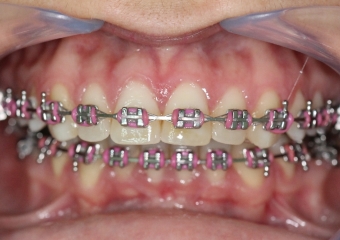

Mordida inicial